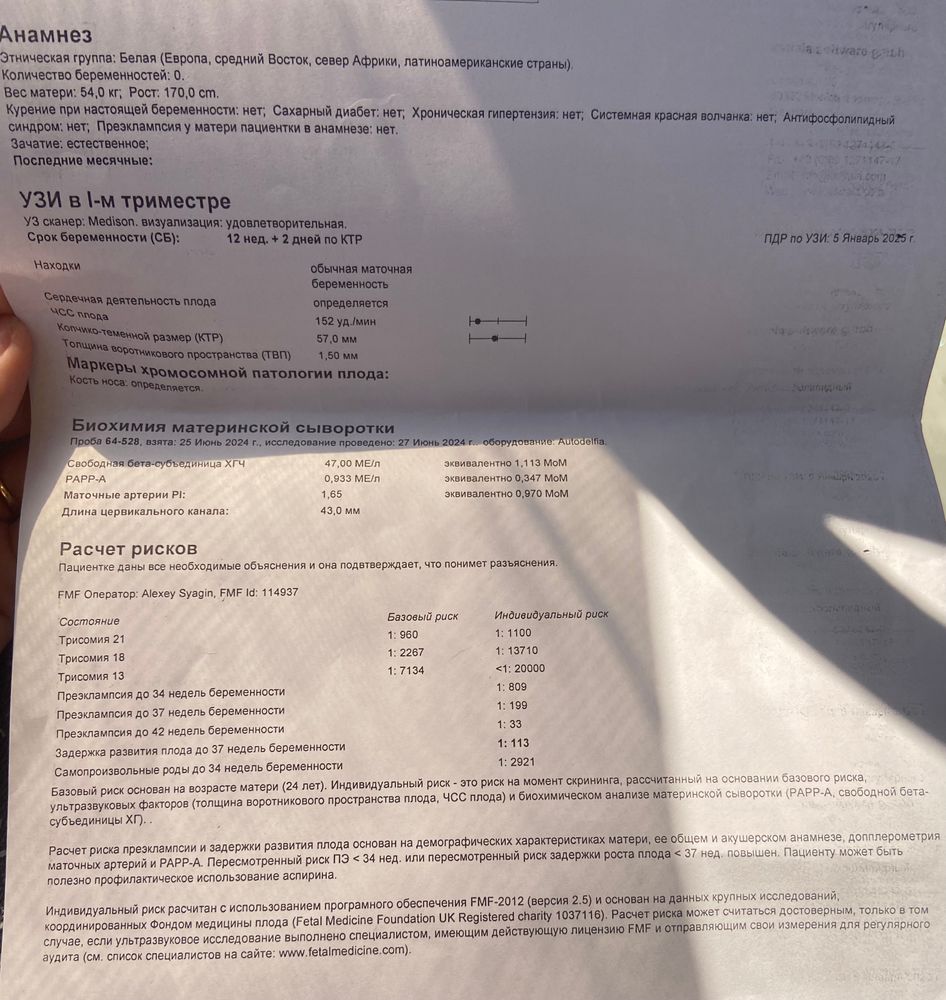

я вот все думаю, низкий ли риск трисомия 21- 1:1100?

Вообще в совокупности по всему скринингу- все хорошо ведь? Хочется успокоится до приема врача ( а прием 11 июля только😁)

я вот все думаю, низкий ли риск трисомия 21- 1:1100?

Вообще в совокупности по всему скринингу- все хорошо ведь? Хочется успокоится до приема врача ( а прием 11 июля только😁)

1:100- высокий

Трисомия 21 1:1100 низкий риск. Вопросы по преэклампсии и задержке развития (кровотоки нужно смотреть)